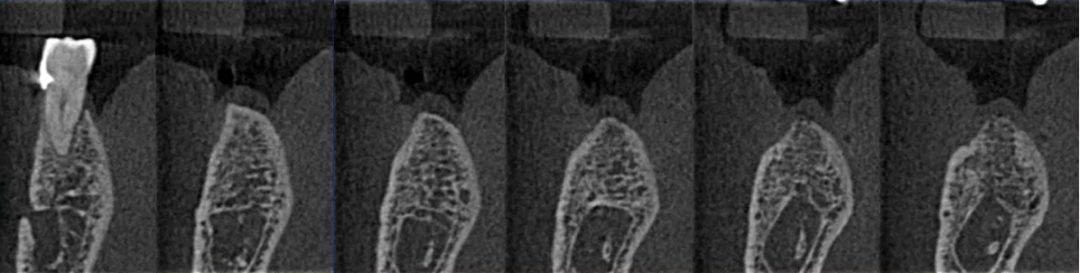

进一步检查:口腔CBCT的应用

36、46根管评估,45根尖颏孔鉴别诊断

曲面断层片怎么看口腔精读 | 一次性教你看懂曲面断层片!_https://www.jmylbn.com_新闻资讯_第48张

曲面断层片怎么看口腔精读 | 一次性教你看懂曲面断层片!_https://www.jmylbn.com_新闻资讯_第49张

42根尖区低密度影鉴别诊断

曲面断层片怎么看口腔精读 | 一次性教你看懂曲面断层片!_https://www.jmylbn.com_新闻资讯_第50张

38根尖区高密度影鉴别诊断

曲面断层片怎么看口腔精读 | 一次性教你看懂曲面断层片!_https://www.jmylbn.com_新闻资讯_第51张

下颌种植主要判断:神经管走行及位置

左侧神经管下壁显示清晰,但上壁右侧神经管不清晰,前段疑似膨大。

局部小视野CBCT检查

曲面断层片怎么看口腔精读 | 一次性教你看懂曲面断层片!_https://www.jmylbn.com_新闻资讯_第65张

神经管位于46、47位置膨大,上壁不清。